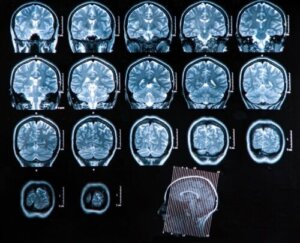

- Datortomografi: Detta har stor diagnostisk användbarhet, eftersom det gör att man kan kontrollera eventuella kopplingar till det medicinska tillståndet och fastställa behandling enligt motsvarande fas. Denna teknik är också effektiv för att följa upp utvecklingen av sjukdomen efter behandlingen.

- Magnetisk resonanstomografi: Detta är den bästa typen av avbildningsstudie vid diagnos av en hjärnabscess. Det är mycket känsligare än datortomografi och erbjuder många fördelar vid upptäckt av tidig cerebrit och ödem och bättre differentiering mellan områden med inflammation och andra påverkade strukturer.